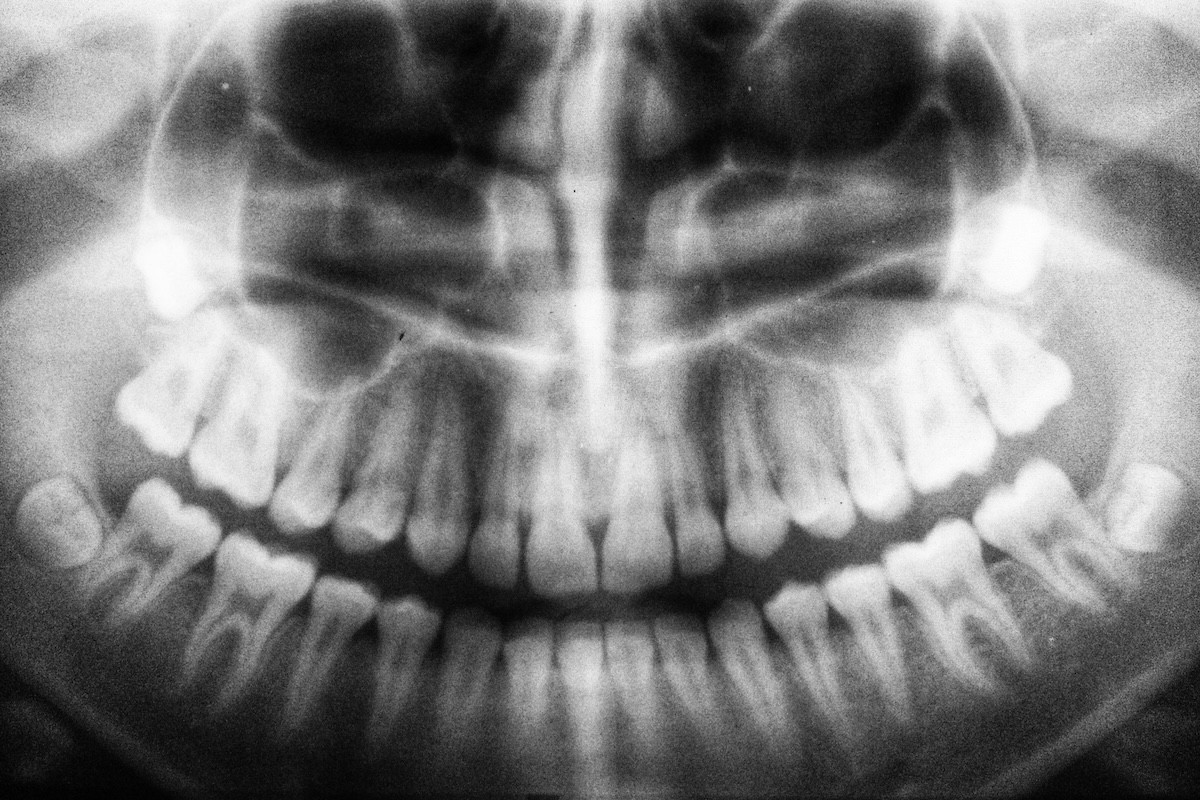

Ο ρυθμός με τον οποίο χάνονται τα δόντια σε μεγαλύτερη ηλικία φαίνεται ότι συνδέεται με τον κίνδυνο θανάτου, σύμφωνα με νέα εκτενή μελέτη που δημοσιεύθηκε στο περιοδικό BMC Geriatrics.

Τα ευρήματα της συγκεκριμένης μελέτης υπογραμμίζουν τη σημασία της καλής στοματικής υγείας και δείχνουν ότι η απώλεια δοντιών μπορεί να αποτελεί ένδειξη σοβαρότερων προβλημάτων υγείας.

Η απώλεια δοντιών έχει συνδεθεί και στο παρελθόν με αυξημένη θνησιμότητα. Γενικά, όσο λιγότερα δόντια έχει κάποιος, τόσο μεγαλύτερος είναι ο κίνδυνος πρόωρου θανάτου. Ωστόσο, μέχρι σήμερα δεν υπήρχαν στοιχεία για το πώς ο ρυθμός απώλειας των δοντιών επηρεάζει αυτή τη σχέση.

Για να απαντήσουν σε αυτό το ερώτημα, ερευνητές από το Πανεπιστήμιο Sichuan στην Κίνα παρακολούθησαν 8.073 ηλικιωμένα άτομα, εξετάζοντας τον ρυθμό με τον οποίο έχαναν δόντια και τη συσχέτιση με τη θνησιμότητα, σε διάστημα περίπου 3,5 ετών.

Οι επιστήμονες δεν υποστηρίζουν ότι η γρήγορη απώλεια δοντιών προκαλεί τον θάνατο, αλλά ότι τα προβλήματα υγείας που οδηγούν σε απώλεια δοντιών μπορεί να επηρεάζουν και τη μακροζωία. Έτσι, η απώλεια δοντιών θα μπορούσε να λειτουργήσει ως δείκτης για την εκτίμηση της συνολικής υγείας και του κινδύνου θνησιμότητας ενός ατόμου.